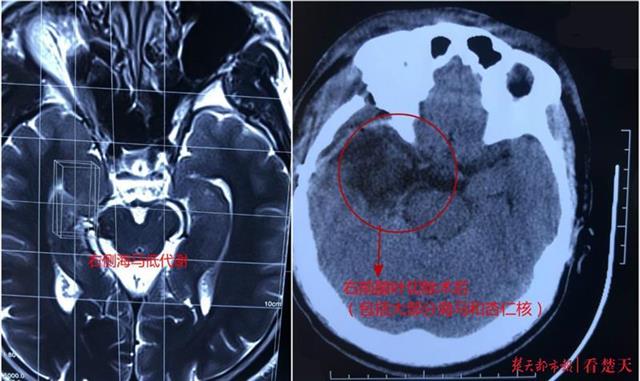

术前术后

检查排除了脑肿瘤、脑血管病、脑外伤等继发性病因后,患者右侧大脑海马代谢减低的结果引起了接诊专家王焕明教授的注意,凭借丰富的顽固性癫痫诊疗经验,进一步完善检查,郑先生被确诊为右侧伴海马硬化颞叶内侧癫痫 。王焕明解释,因患者右侧海马组织先天发育不良,随着年龄增长逐渐产生海马硬化及缩小,引发代谢异常,便产生了波及右侧颞叶内侧及颞极区脑部的异常放电,出现四肢抽搐、发作时失忆等典型颞叶癫痫症状 。

考虑郑先生病程较长,症状较重,多种抗癫痫药物已无法控制,王焕明及时为他进行了右前颞叶切除手术 。全麻后,在手术显微镜的辅助及皮层脑电图的监测下,王焕明带领陈俊、陈阳和王杰等手术医师,经右额颞扩大冀点入路,小心精准定位右侧颞叶异常放电区域,顺利全切了右侧前颞叶和大部分海马及杏仁核等病灶 。术后经半月恢复至今,郑先生的癫痫再未发作,即将痊愈出院 。